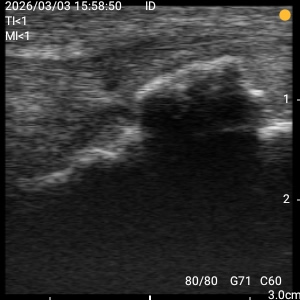

右膝 オスグッド 大阪市旭区 男性小学生 バスケットボール

右膝オスグッド病 圧痛、運動時痛、ストレッチ痛あり

骨隆起、圧痛、も健側と比較し著名